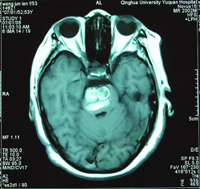

53岁的王女士,今年初在北京三博复兴脑科医院被诊断患有“桥脑巨大海绵状血管瘤”。近日,该院石祥恩教授、吴斌主任为其实施了“右颞枕开颅、桥脑海绵状血管瘤全切除术”。手术中发现,该血管瘤几乎占据了整个桥脑位置,大小约为4.0 cm×3.5 cm×3.5 cm,十分罕见。术后,患者恢复顺利,已痊愈出院。